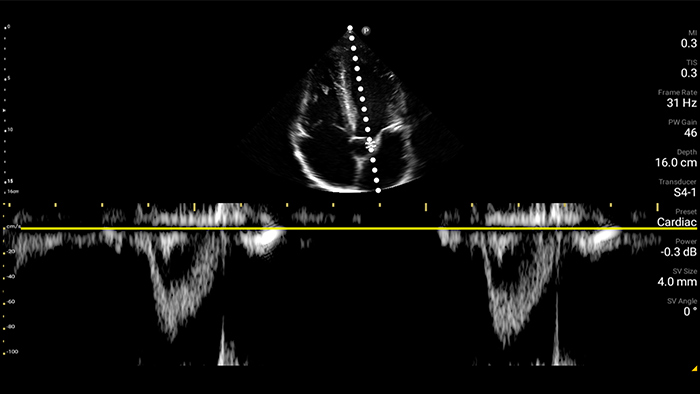

Przedszpitalna echokardiografia serca: zator płucny

Podstawy ultrasonografii płuc